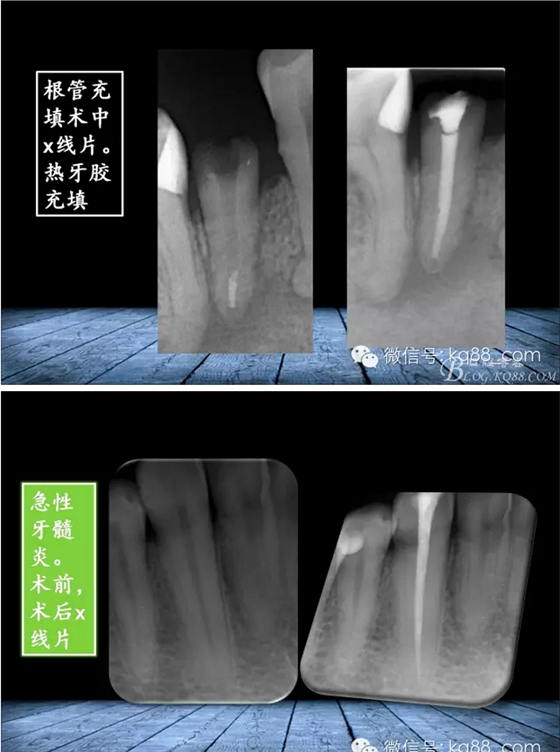

QQ圖片20150817140856.png

QQ圖片20150817140915.png